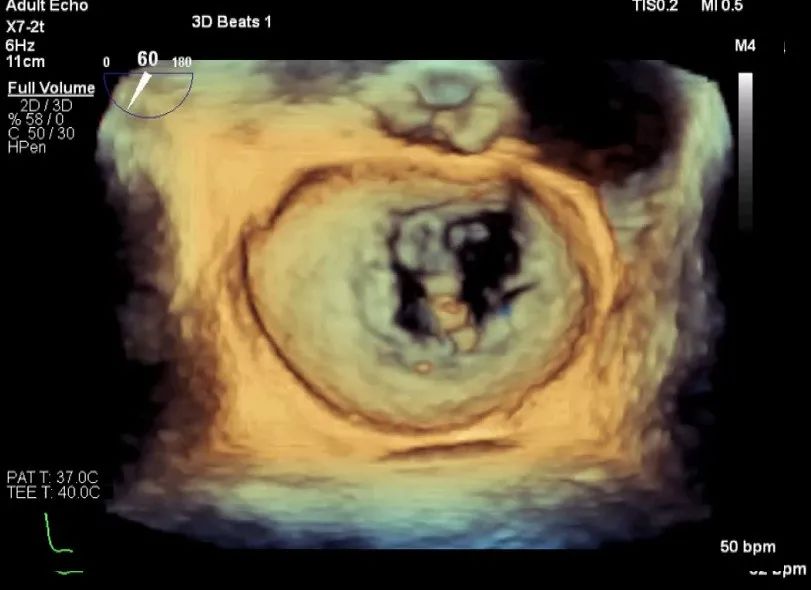

术前超声评估

术前超声诊断

LVOT-color:MR(重度),返流面积11.3cm2

肺静脉血流频谱呈收缩期反向

3D-color MV view:血流主要来源于2、3区

Qlab软件勾画估测瓣口面积约:6.16cm2

TEE LVOT切面返流量评估

TEE 4-Ch view返流量评估

术中超声

确定房间隔穿刺点:靠后

2D视图下测量大鞘长度2cm

3D视图打开夹子

X-plane:下第夹子尝试捕获2区

X-plane:测量前叶长25mm,后叶长14.2mm

X-plane:计算前叶捕获长度8mm,后叶捕获长度7mm

3D视图下观察二尖瓣双孔形态

3D-color:残余少量返流